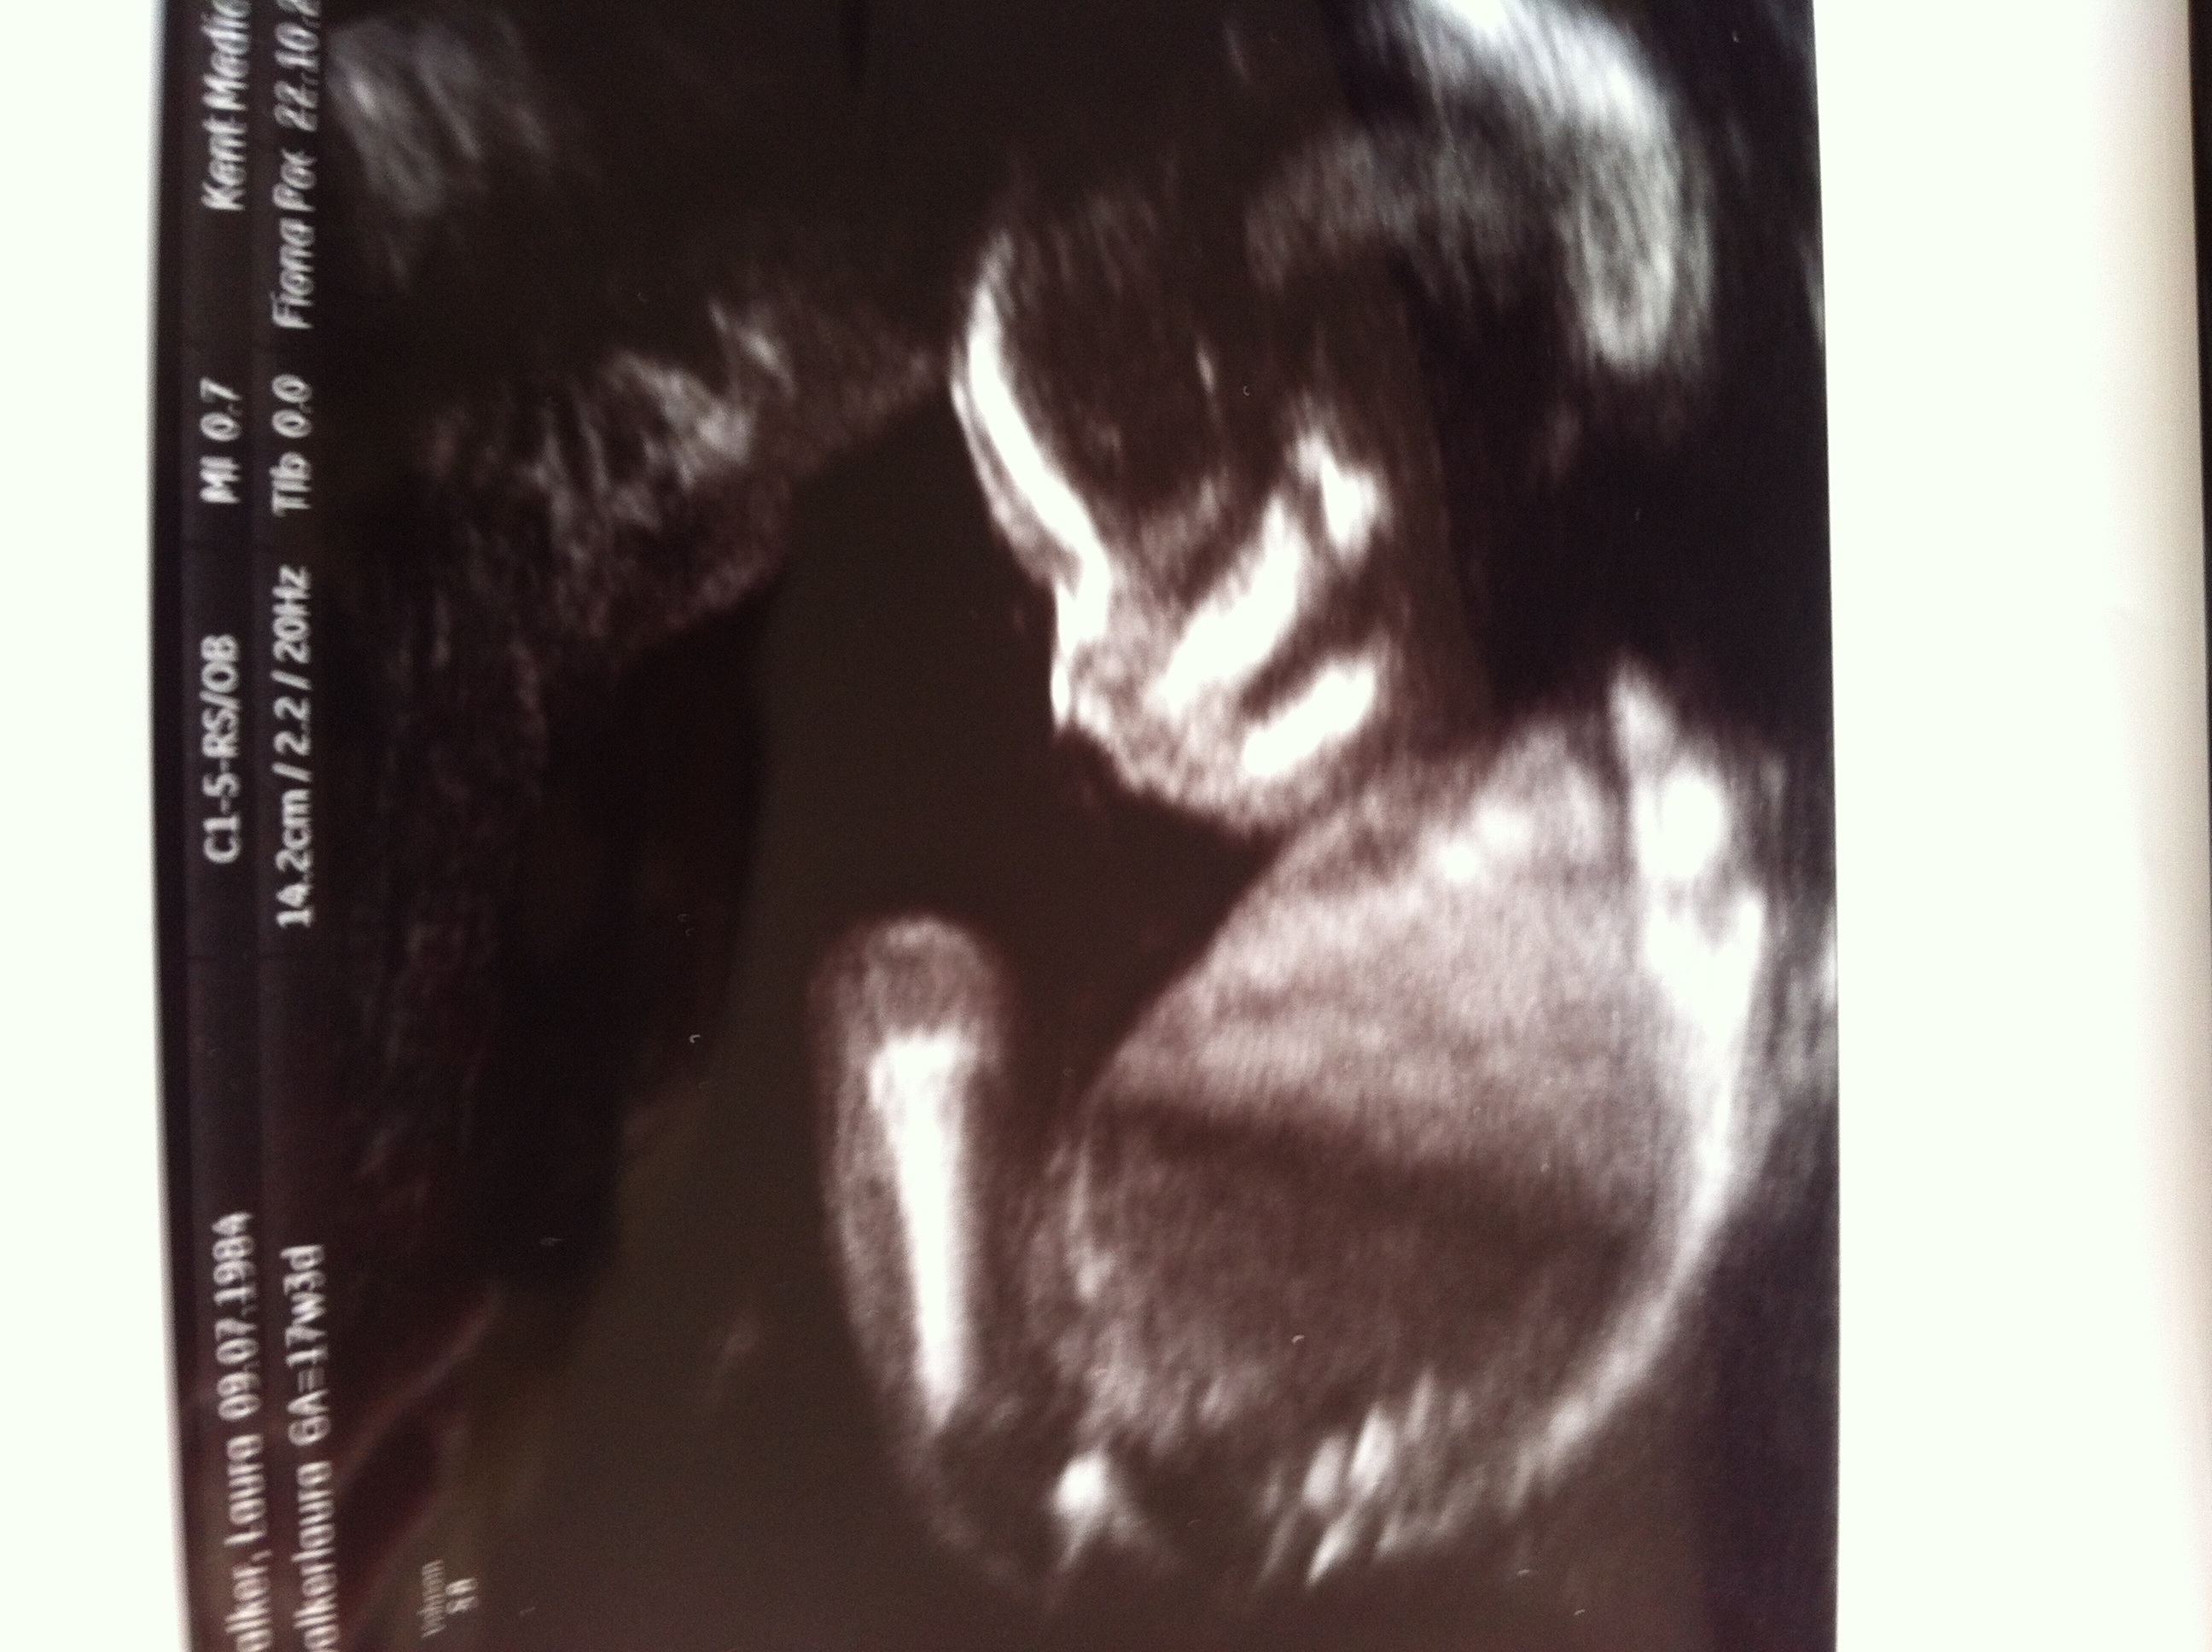

How Accurate Is A Gender Ultrasound At 17 Weeks

17 weeks ultrasound Boy?? Girl?? Van Tilden. maybe girl, but still hard to tell. it's driving me nuts!!! haha which is it? any guesses?? we will get a more accurate answer next time in 3 more weeks! 16 weeks + 6 days ultrasound gender scan, 3d + 4d - Duration: 9:06. ... View Video